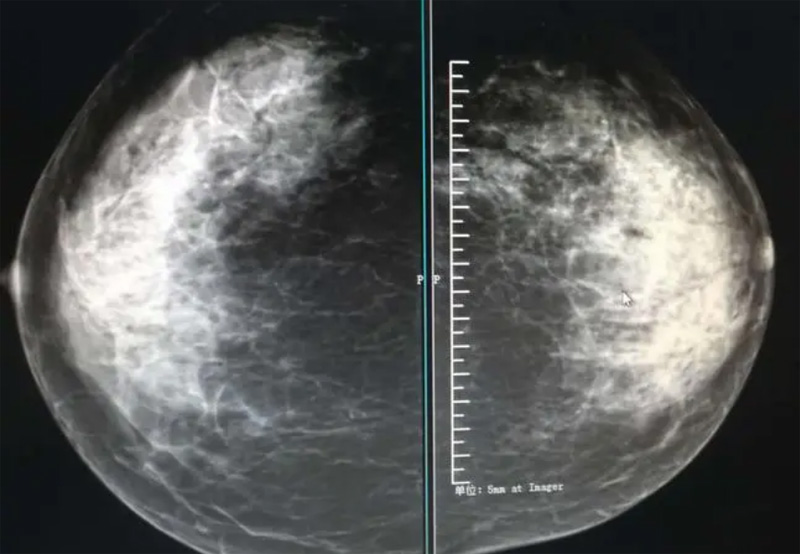

攝影診斷規(guī)范乳腺DR有頭尾位及內(nèi)外側(cè)斜位診斷概念和診斷術(shù)語

乳腺DR的檢查中為了讓乳腺相關(guān)疾病的篩查需要更高質(zhì)量的檢查圖像。檢查前期的準(zhǔn)備工作非常重要。醫(yī)生跟病患的有效溝通。要跟檢查者說明檢查過程,特別是體位跟擠壓乳房帶來的不適應(yīng)。放松心情,檢查過程中得到充分的合作。正確的擺正位置乳腺DR可以拍攝到更優(yōu)質(zhì)清洗高質(zhì)量的X線圖像。乳腺DR檢查需要再月經(jīng)后檢查,但是對病癥明顯的就不受這個限制。

乳腺DR攝影體位有頭尾位及內(nèi)外側(cè)斜位,

乳房在片子的中央,乳頭切線位,可見小部分胸大肌,內(nèi)側(cè)乳腺組織應(yīng)全部包括在片中,外側(cè)乳腺組織盡可能包括在片中。一張好的MLO位圖像顯示如下:乳房被推向前上,乳腺實質(zhì)充分展開,胸大肌可見,較松弛,下緣達(dá)到乳頭水平,乳頭在切線位,部分腹壁包括在片中,但與下部乳腺分開,絕大部分乳腺實質(zhì)顯示在片中。乳腺組織外緣可見乳頭的輪廓;乳腺后方的脂肪組織被很好地顯示出來,乳房無皺褶。對于CC位及MLO位顯示不良或未包全的乳腺實質(zhì),可以根據(jù)病灶位置的不同選擇以下體位:外內(nèi)側(cè)位(LM)、內(nèi)外側(cè)位(ML)、內(nèi)側(cè)頭尾軸位(MCC)、外側(cè)頭尾軸位(LCC),尾葉位(CLEO)及乳溝位。在臨床實踐中,對于常規(guī)體位上發(fā)現(xiàn)的異常改變,可以進(jìn)一步采取一些特殊的攝影技術(shù),包括局部加壓攝影、放大攝影或局部加壓放大攝影技術(shù)。